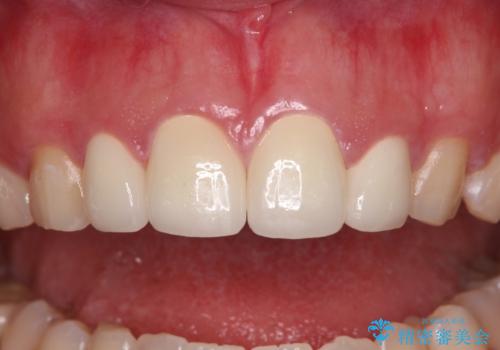

前歯の捻れは、オールセラミッククラウンよりも矯正治療による改善の方が、歯を削らなくて済むためお勧めとなります。

しかし、矮小歯の改善はオールセラミッククラウンでの補綴治療が必要であり、幅径のバランスを取る必要があるため、4前歯の補綴治療を選択しました。